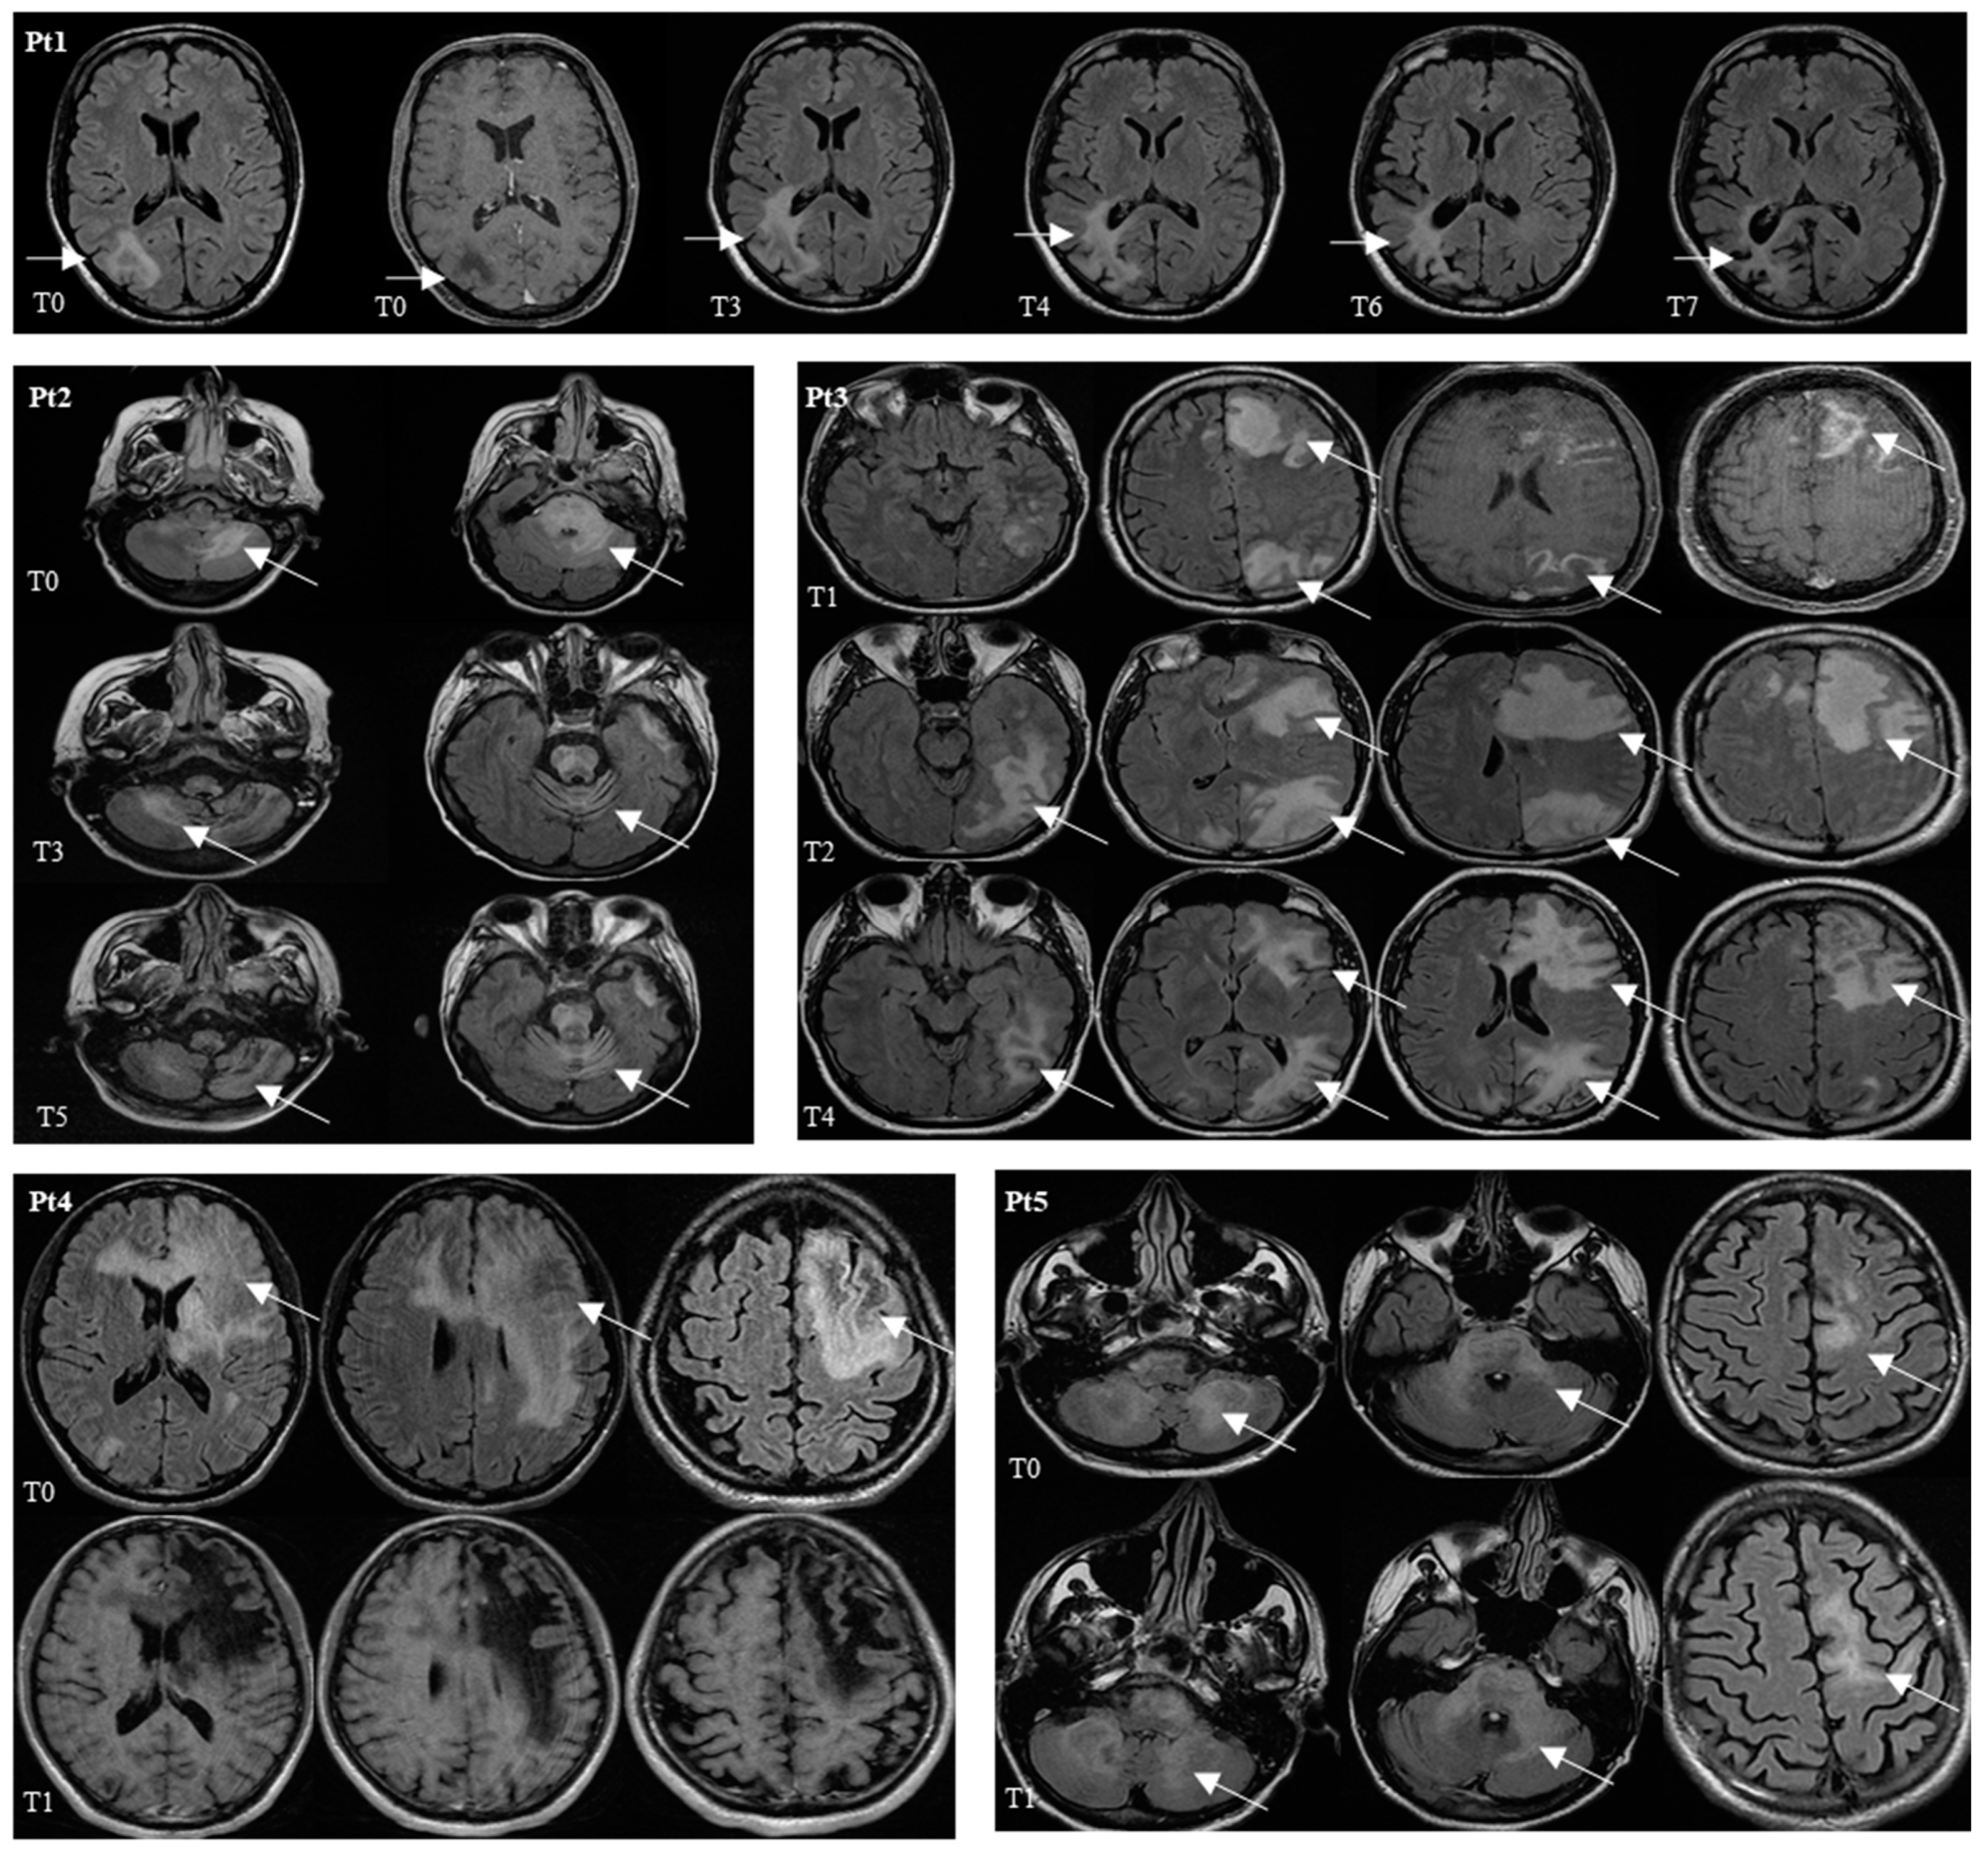

| Patients’ Characteristics | Pt 1: M, 52 years old, MSM CDC-C3 (Kaposi’s Sarcoma) Previously: R-CHOP for Castelman Disease (2014), ABVD for Hodgkin Lymphoma (2019) KS 80 | Pt 2: F, 46 years old, IDU CDC-B3 at diagnosis of HIV Previously: HCV-Ab, arterial hypertension, thyreopathy, psychosis KS 50 | Pt3: M, 36 years old, MSM CDC-C3 at diagnosis of HIV (PCP) No other comorbidities KS 70 | Pt 4: M, 43 years old, MSM CDC-A2 (PHI) Previously: syphilis KS 60 | Pt 5: M, 30 years old, MSM CDC-C3 (PML) Previously: gastritis KS 50 |

| cART History | 2012 to 2016 FTC/TDF/EFV→FTC/TDF/RPV Off therapy until 2019 At T0: FTC/TDF/DTC | Off therapy At T0: FTC/TDF/DTG | Off therapy At T0: BIC/F/TAF | From 2012 to 2016 FTC/TDF/DRV/r→ FTC/TDF/DRV/c→ E/c/FTC/TAF Off therapy since 2016 At T0 (2020): FTC/TAF/DRV/c+DTG | Start 1 month before PML diagnosis with FTC/TAF/BIC+DRV/c |

| Viro-Immunological Assessment | At T0: CD4 T 282 cells/mmc (15.6%) HIV RNA <30 cps/mL CSF JCV DNA 262,800 cps/mL At T7: CD4 T 264 cells/mmc (13%) HIV RNA <30 cps/mL CSF JCV DNA 20 cps/mL | At T0: CD4 T 158 cells/mmc (11.2%) HIV RNA 5,950,845 cps/mL CSF JCV DNA 9540 cps/mL At T5: CD4 T 276 cells/mmc (17.5%) HIV RNA <30 cps/mL CSF JCV DNA 33 cps/mL | At T0: CD4 T 89 cells/mmc (6.8%) HIV RNA 619 cps/mL CSF JCV DNA 183 cps/mL At T5: CD4 T 55 cells/mmc (6%) HIV RNA <30 cps/mL CSF JCV DNA 43 cps/mL | At T0: CD4 T 64 cells/mmc (13.2%) HIV RNA 28,344 cps/mL CSF JCV DNA 338,910 cps/mL At T2: CD4 T 75 cells/mmc (11.5%), HIV RNA <30 cps/mL CSF JCV DNA 10 cps/mL | At T0: CD4 T 15 cells/mmc (2.2%), HIV RNA 351 cps/mL CSF JCV DNA 14,430 cps/mL At T2: CD4 T 35 cells/mmc (4.5%) HIV RNA 170 cps/mL CSF JCV DNA 33 cps/mL |

| Neurological Signs/ Symptoms | Left hemianopia and loss of vision | Ataxia, loss of vision, left dysmetria and psychosis | Aphasia, confusion and comitial crisis | Aphasia and faciobrachial crural hemiparesis | Cognitive impairment, behavioral disturbances, progressive facio-brachial-crural hemiparesis, aphasia |

| Clinical Outcomes | Clinical and radiological improvement |

Lack of evolution Clinical and radiological stability | Clinical and radiological improvement | Death due to sepsis | Death due to sepsis |